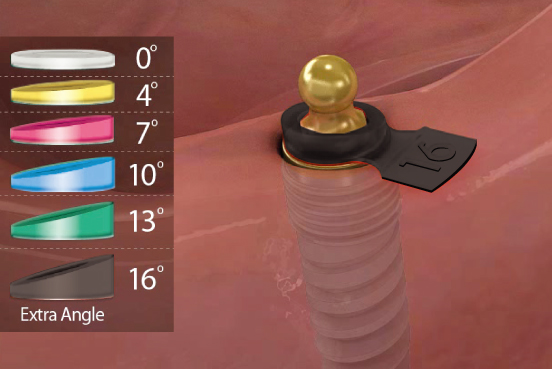

편측 20도 각도 보상

편측 20도 각도 보상지대주의 groove와 housing ball & spring이 체결되는 ‘EZ LOCKING 방식’에 의해 fixture의 식립각도를 20도까지 보상할 수 있다. (각도별 housing positioner 이용)

- Fixture의 식립방향에 따라 Housing Positioner를 선택▼

- H/P를 끼우고 좌우로 움직이면서 교합면과 평행하게 Housing 장착▼

- Fixture의 식립방향에 따라 Housing Positioner를 선택▼